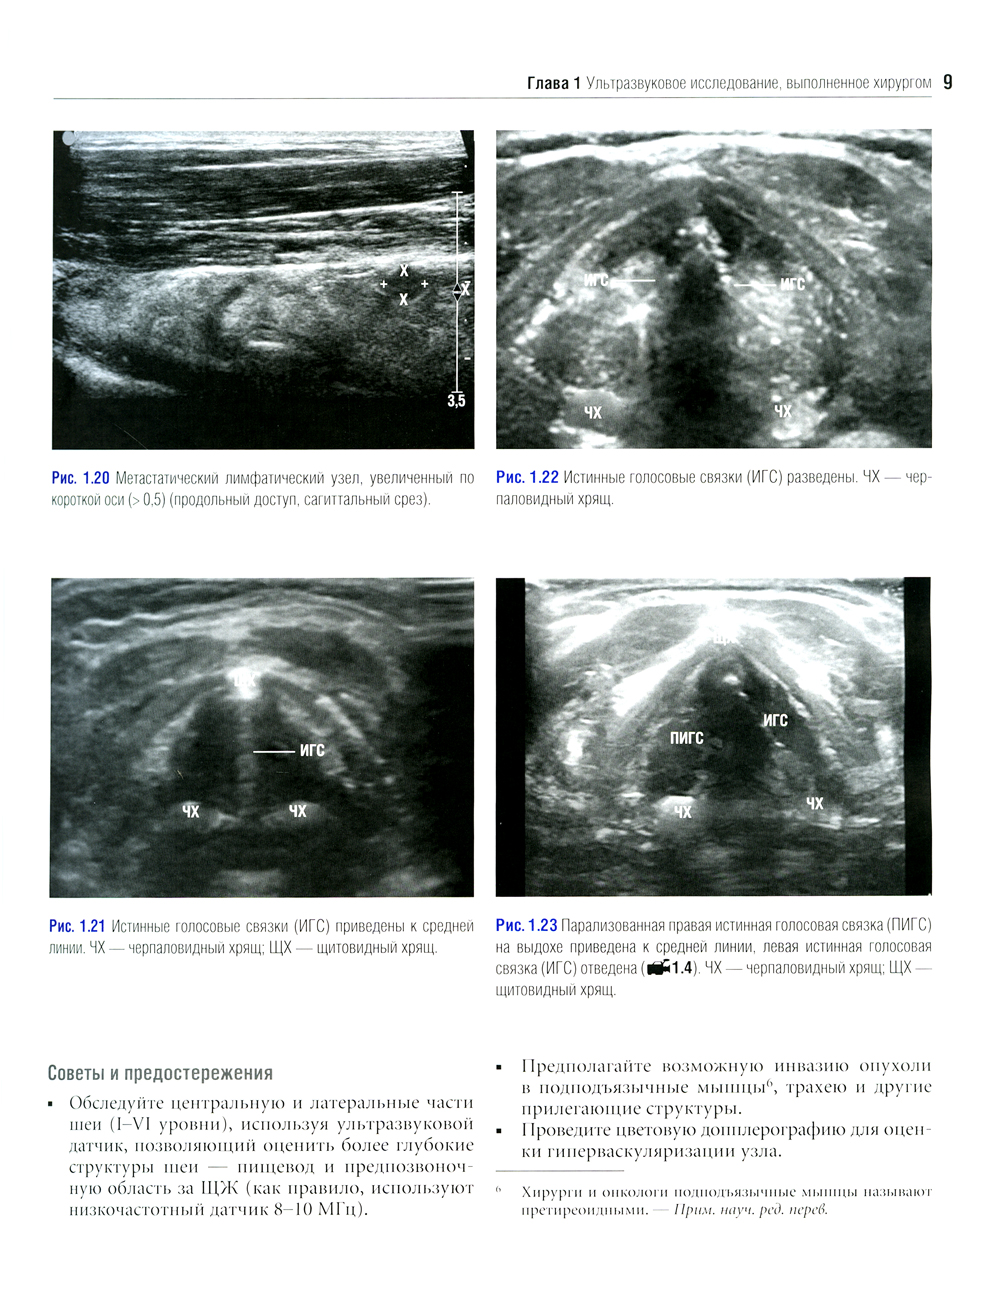

Данное издание представляет собой великолепно иллюстрированный хирургический атлас. В нем рассмотрены методы ультразвукового исследования шеи, молекулярно-генетическое тестирование пациентов с узловыми образованиями в щитовидной железе, робот-ассистированные хирургические методы, техника эндоскопических операций при эндокринных опухолях, хирургия при рецидиве заболевания, аутотранснлантация и криоконсервация околощитовидных желез, адреналэктомия при метастазе в надпочечнике, хирургия нейроэндокринных опухолей тонкой кишки и их метастазов в печени. «Атлас эндокринной хирургии» состоит из 4 частей: «Хирургия щитовидной железы», «Хирургия околощитовидных желез», «Хирургия надпочечников», «Хирургия опухолей поджелудочной железы и карциноидов». Всего в издании 29 глав, подготовленных сотрудниками экспертных факультетов ведущих медицинских школ США, Европы и Азии. Каждая глава состоит из разделов, в которых описаны общие сведения, показания и противопоказания, оценка риска, алгоритм принятия решений и планирование вмешательства, необходимое оборудование и материалы, хирургические техники, результаты лечения, осложнения и последующее наблюдение, а также даны советы и предостережения авторов. В книге много информации, которой нет в других источниках. Наряду с многочисленными фотографиями, сделанными в ходе операций, а также данными, полученными при различных методах визуализации, приведено значительное количество иллюстраций и видеоматериалов, демонстрирующих хирургическую технику или обследование. Издание предназначено практикующим врачам в области эндокринной хирургии, специалистам в смежных областях медицины и студентам медицинских высших учебных заведений.| Издательство | Логосфера |